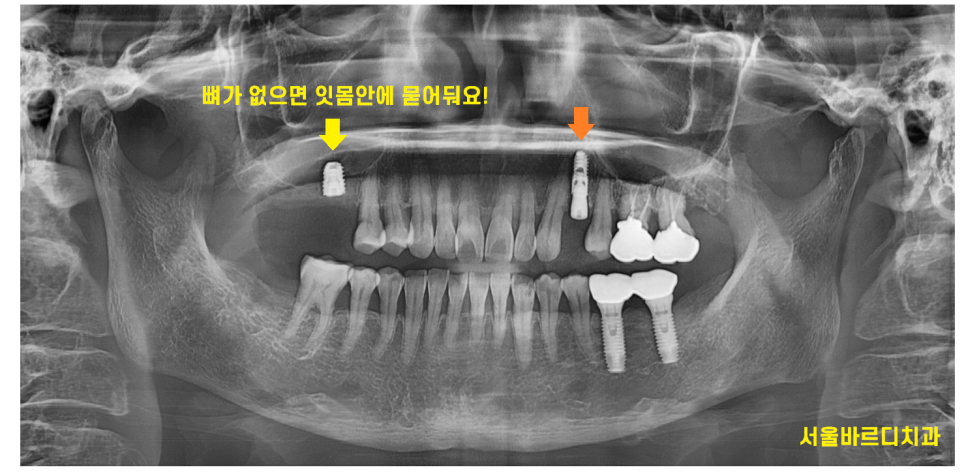

241220 나이가 젊어도 뼈가 없으면 임플란트 식립이 어렵습니다.

뼈 상태를 보아야한다!!

잇몸뼈만 충분하고 튼튼하면

임플란트는 잘 고정될 수 있답니다.

250317 뼈 상태에 따라 수술법이 달라집니다.

너무 어린 성장기만 아니라면

치료는 가능하다!!